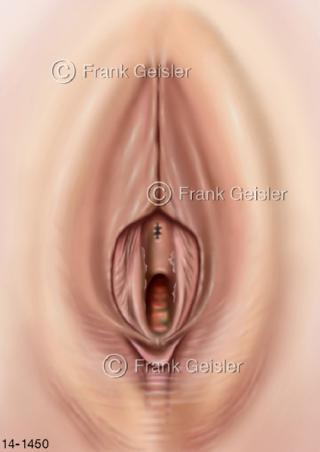

Bildergalerie Urogenitalsystem

Bilder zum Urogenitalsystem mit Urogenitalorgane, Urogenitaltrakt, zum Harn- und Geschlechtsapparat, Harnorgane und Geschlechtsorgane, Organe der Harnwege und der Fortpflanzung, Harnorgane und Geschlechtsorgane im männlichen und weiblichen Urogenitalsystem